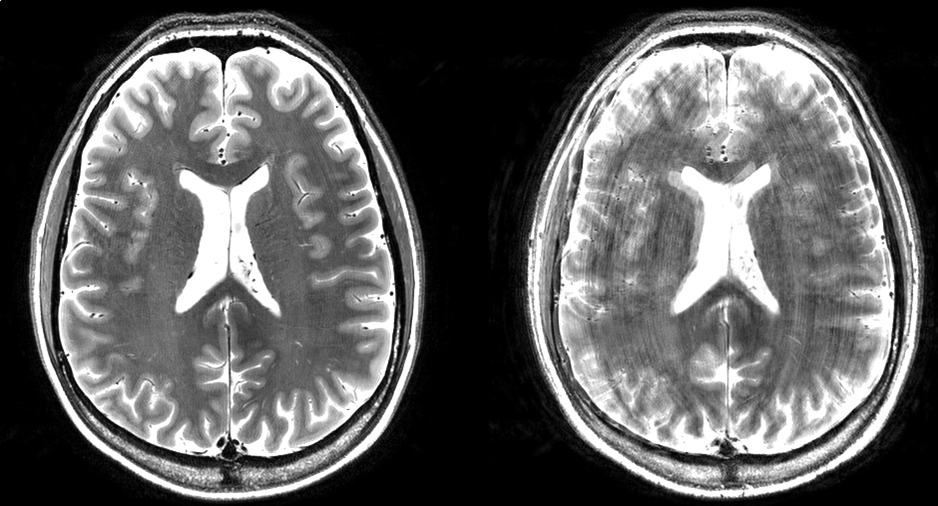

- The improved signal-to-noise at 7 tesla allows submillimeter structural and functional image resolution which offers new insights into the understanding of the organization and processes of the body in health and disease. However, a good compensation of subject motion is required to avoid image degradation, which would defeat the purpose of ultra-high resolution imaging. We work on fast image readout approaches and navigator-based correction methods to reduce the effects from motion and the increased physiological noise we unfortunately experience at higher field strength.

Mads Andersen and Vincent Boer are developing techniques to update the position of the imaging/spectroscopy volume in real-time, as small head motion occur during scanning. Motion is monitored using extra sequence modules (navigators) that acquire dynamic MR data in pauses of the target imaging/spectroscopy sequence.

Figure 1: High resolution T2-weighted images acquired at 7T in a subject who moved during the scan. The left image was acquired with motion correction; the right image was acquired without motion correction. The motion was similar in timing and magnitude for the two acquisitions.